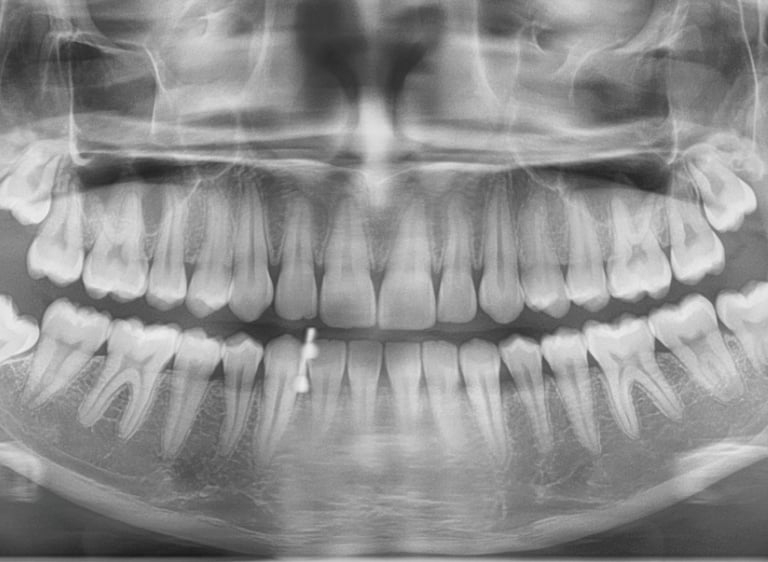

Dente deitado

Dente inclinado